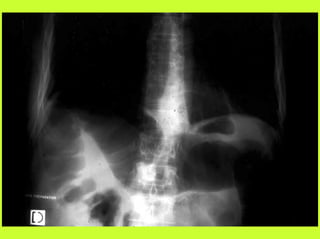

3) RADIO (PNO)

RADIOGRAPHIES

ABDOMEN SP -scanner

PNEUMOPERITOINE SUR SUJET DEBOUT

" Croissant gazeux sous diaphragmatique

" Disparition du niveau hydroaérique gastrique

PNEUMOPERITOINE SUR SUJET COUCHE

" Visibilité du ligament triangulaire du foie

" Visibilité anormale des parois intestinales

" Image aérique pré-hépatique

"Pneumatisation de MORRISSON

(cul de sac inter-hépato-rénal)

PERITONITES PAR PERFORATION

COLIQUE

! Gravissime

! Péritonite stercorale

! Douleurs abdominales diffuses

! Choc toxi-infectieux - T°39°

! Contracture ou métérorisme

! ASP, pneumopéritoine important